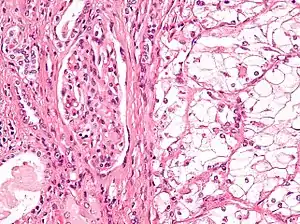

The most common type of kidney malignancy is renal cell carcinoma,[31] which is thought to originate from cells in the proximal convoluted tubule of the nephron.[12][32] Another type of kidney cancer although less common, is transitional cell cancer (TCC) or urothelial carcinoma of the renal pelvis.[33] The renal pelvis is the part of the kidney that collects urine and drains it into a tube called the ureter.[33] The cells that line the renal pelvis are called transitional cells, and are also sometimes called urothelial cells. The transitional/urothelial cells in the renal pelvis are the same type of cells that line the ureter and bladder. For this reason TCC of the renal pelvis is distinct from RCC and is thought to behave more like bladder cancer.[33] Other rare types of kidney cancers that can arise from the urothelial cells of the renal pelvis are squamous cell carcinoma and adenocarcinoma.[12]

Renal cell carcinoma has been further divided into sub-types based on histological features and genetic abnormalities. The 2004 WHO Classification of the Renal Tumors of the Adults describes these categories:[37]

- Clear cell RCC